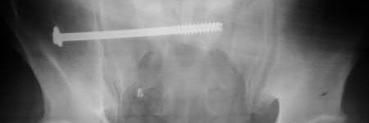

A 44-year-old male presents with the isolated injury seen in Figure A after a motor vehicle accident and underwent the operative treatment seen in Figure B within 8 hours from the time of incident. Which of the following complications is this patient at highest risk of developing?

This young male patient has sustained a displaced femoral neck fracture and underwent open reduction internal fixation with 3 cannulated screws. Based on the available options, the patient is most at risk of developing osteonecrosis of the femoral head.

Femoral neck fractures in young patients typically are the result of a high-energy trauma. Fracture displacement has been shown to disrupt vascular supply to the femoral head by interrupting retinacular vessels and ligament teres vascularization, as well as increasing intracapsular pressure, producing a tamponade effect. The incidence of osteonecrosis in patients younger than 60 years with displaced femoral neck fractures has been shown to be between 15-30%. Quality of reduction is one key factor that has been shown to influence outcomes postoperatively.

Loizou et al. prospectively studied 1,023 patients who sustained an intracapsular hip fracture that was treated with internal fixation using standard fixation modalities. They showed that osteonecrosis was less common for undisplaced (4.0%) than for displaced fractures (9.5%). The population at greatest risk were women younger than the age of 60 with displaced fractures.

Barnes et al. review subcapital hip fractures. They found that late segmental collapse was more common in displaced fractures in women younger than age 75 years than in those older than age 75 years treated with internal fixation.

Figure A shows a displaced, Garden 3/Pauwels III hip fracture. Figure B shows anatomical fixation with 3 cannulated screws.